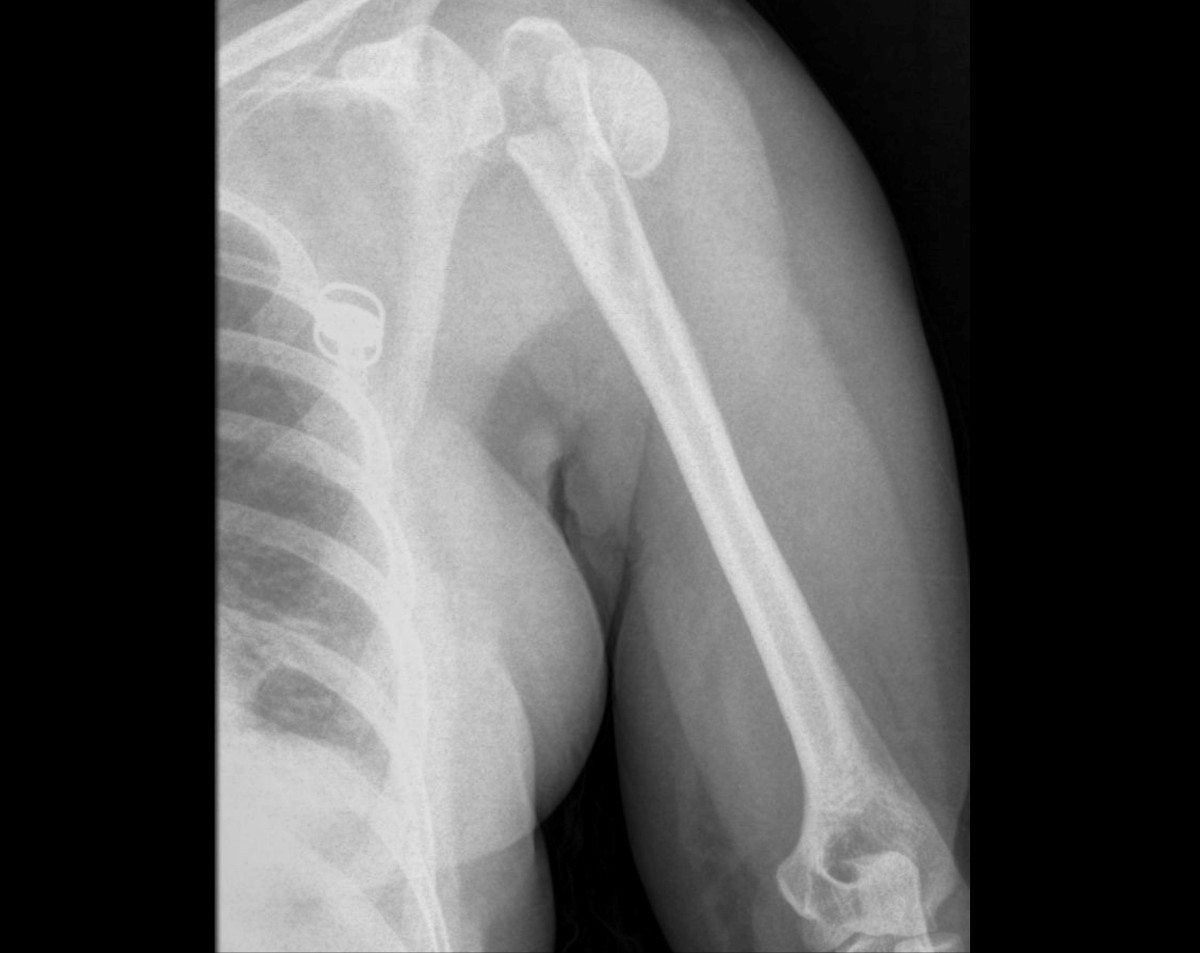

A left Humerus X-ray provides detailed images of the upper arm bone, which extends from the shoulder to the elbow. Physicians use this study to detect fractures, dislocations, bone infections, and degenerative changes. At Desert Mobile Medical, we bring hospital-grade digital X-ray technology directly to you, so you receive accurate diagnostics in the privacy and comfort of your own home, office, or care facility—without the delays of urgent care or hospital visits.

Because it’s quick and reliable, a Humerus X-ray is often the first diagnostic step before advanced imaging such as CT or MRI.